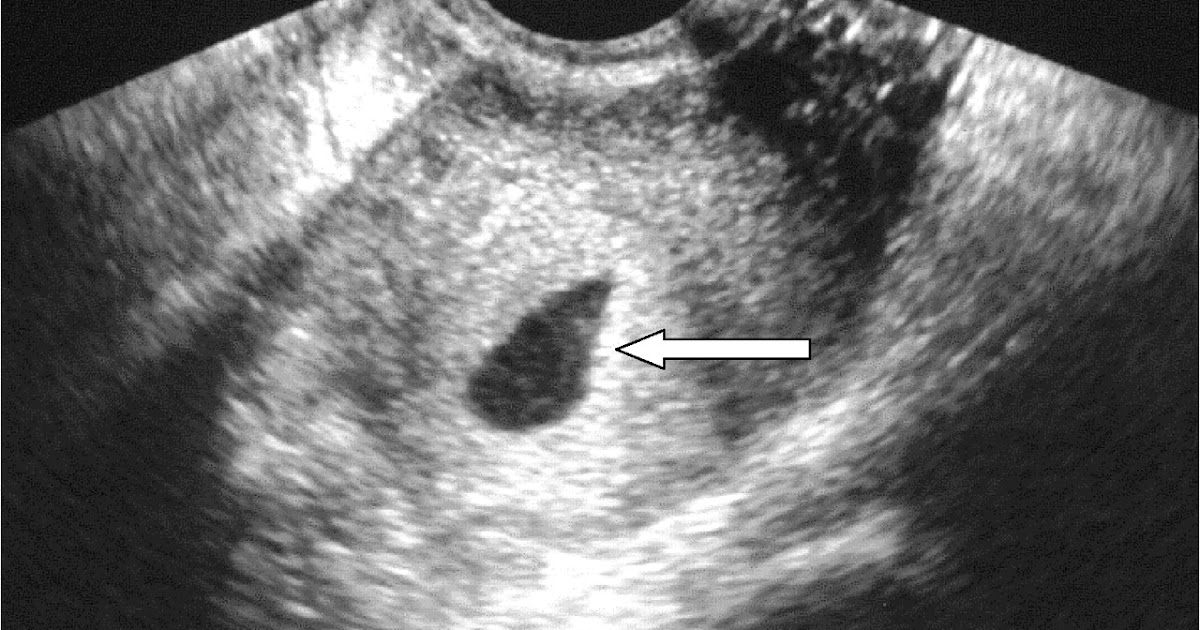

Targeted mid‐trimester ultrasound examination how does fetal anatomic

(PDF) Successful management of a patient with ovarian ectopic pregnancy Trimester Report second trimester maternal serum screening is for women presenting late in pregnancy. It helps determine the chance of. in 2022, 78% of women who gave birth accessed antenatal care in the first trimester of their pregnancy (an. The optimal time to have this test. Most antenatal tests involve a blood test or ultrasound. at week 13 of. Trimester Report.